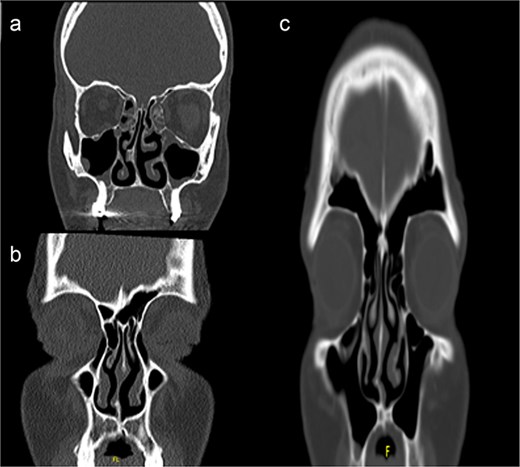

The surgical approach begins with endoscopic visualization of the deviated segment (Fig. 2).

Intraoperative endoscopic view of the deviated nasal septum prior to correction.